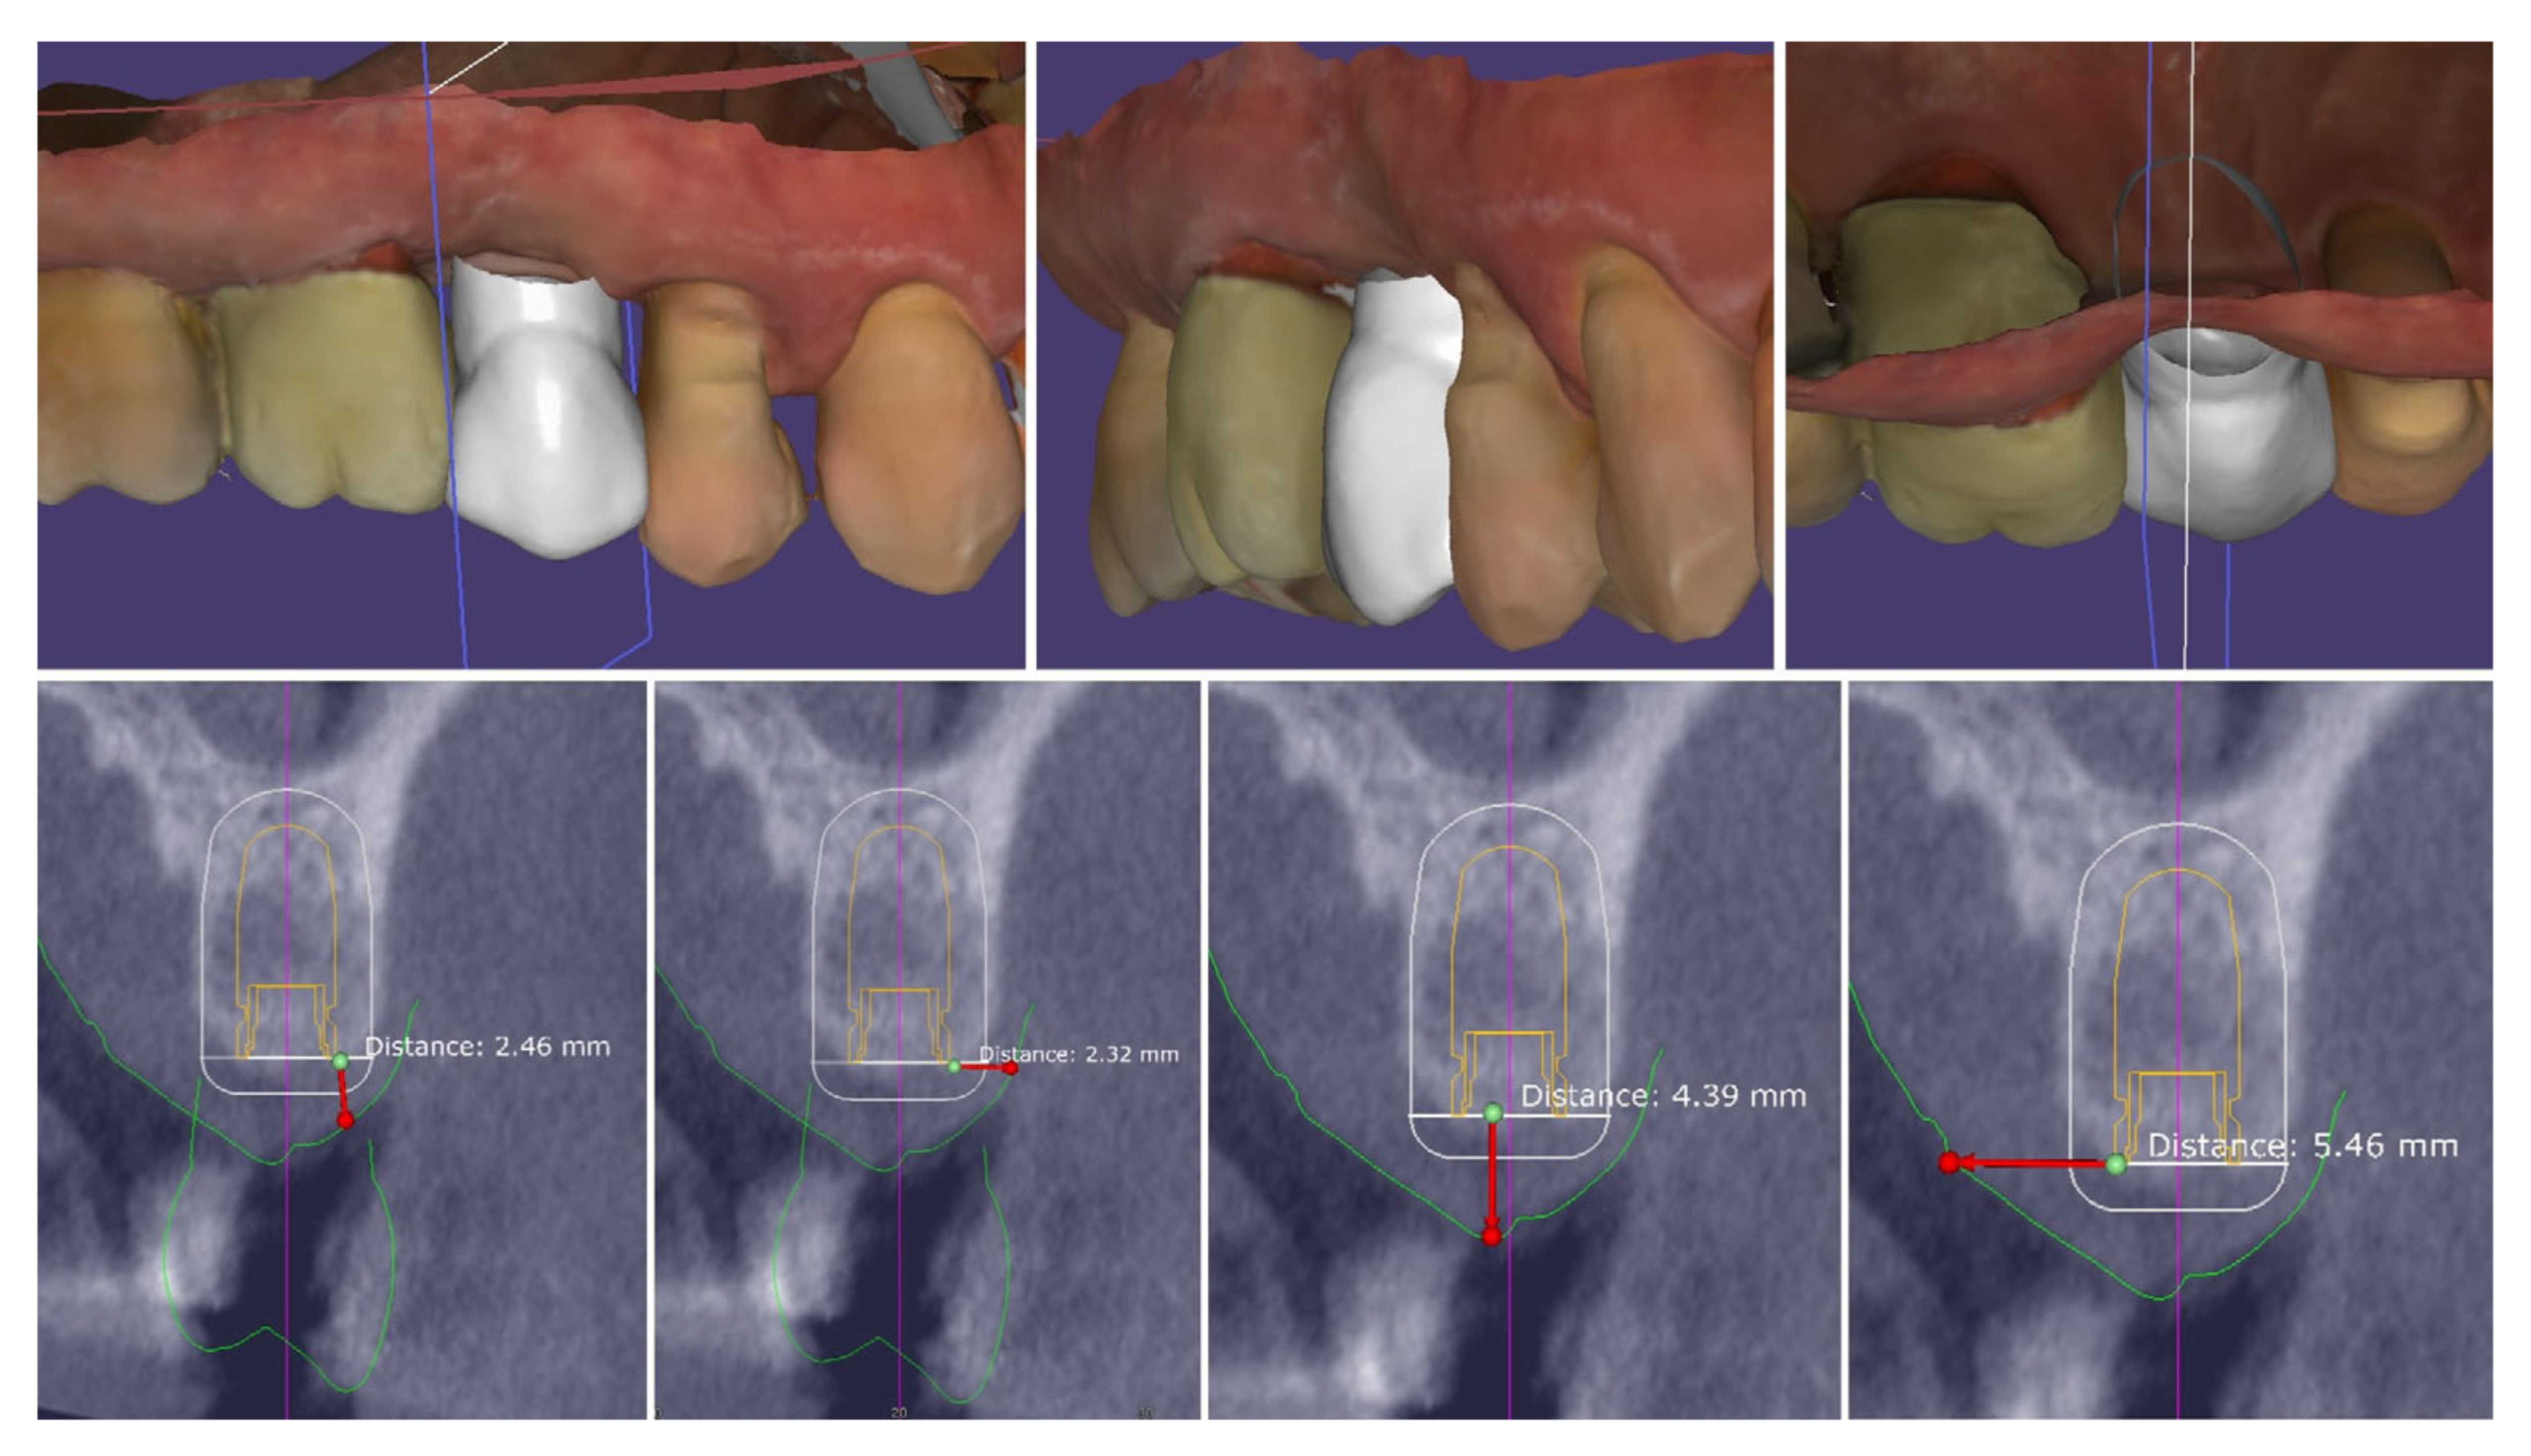

Intraoperatively, the flap preparation included (Figure 7) crestal flap preparation by marking the borders of the implantation area through the surgical guide with the tissue punch followed by crestal U-shaped incision with the blade (15C) perpendicular to crestal mucosa.

Figure 7.

Flap design and flap reflection.

The preservation of unprepared areas of the crestal soft tissue to the adjacent teeth, transformed them into the future peri-implant papillae that can be used to ensure stable primary flap closure, protecting the peri-implant bone from post-surgical resorption.

The U-shaped incision was extended mesially and distally with oblique incisions at the border of the crestal roll flap, separating the peri-implant papillae into anatomic (unprepared part) and surgical parts. The crestal part of the flap was de-epithelized with a 15C blade and microsurgical scissors and was elevated to full thickness with a periodontal chisel (36/37 Rhodes Back-Action chisel, Hu-Friedy, Chicago, IL, USA).

The buccal flap is prepared in partial thickness with the two incisions known from mucogingival surgery, described by De Sanctis and Zucchelli, a split-thickness incision, with the blade parallel to the bone, keeping the periosteum intact, and a split-thickness incision parallel to the external mucosal surface, releasing muscle insertions from the flap. A critical aspect of the procedure was the preservation of the periosteal layer on the buccal wall of the residual socket. This minimally invasive flap design, characterized by split-thickness preparation and the absence of vertical releasing incisions, ensured sufficient vascularization of the flap and minimized the risk of scar formation on the buccal surface [25,26].

The implant was placed using a digitally designed surgical guide to ensure prosthetically driven positioning. Intraoperative images demonstrate the sequence of guided placement: preparation of the osteotomy through the guide with visualization of the prepared site (left), dental implant (T3Pro, ZimVie Inc., Palm Beach Gardens, FL, USA) before placement (middle), and final implant insertion (right) with insertion torque ~50N/cm. The use of a surgical template allowed precise three-dimensional implant placement, optimal angulation, and preservation of surrounding soft and hard tissues (Figure 8).

Figure 8.

Guided implantation protocol.